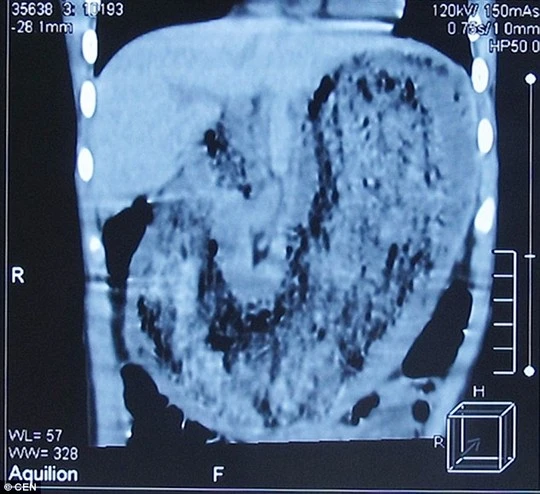

Tại bữa ăn trong tết nguyên đán mới đây, bé gái ngã bệnh nên người cha đã đưa con đến các bác sĩ. Sau khi khám tổng quát, một bác sĩ tại địa phương phát hiện vật lạ giống khối u trong bụng bệnh nhi. Kết quả chụp CT cho thấy trong dạ dày bị lấp đầy bởi một vật lạ nhưng vị bác sĩ chưa kết luận chính xác đó là gì.

Ảnh chụp cho thấy khối tóc trong dạ dày bệnh nhi

Ngày 27-3, bệnh nhi được phẫu thuật thành công và đã được xuất viện trong tuần này. Các bác sĩ lấy ra từ dạ dày bé gái một búi gồm tóc, sợi quần áo, bao bì… nặng gần 2 kg. Búi tóc được kết với nhau khá chặt do tồn tại trong nhiều năm qua, có hình dạng như chiếc dạ dày và ngăn cản việc tiêu hóa thức ăn.